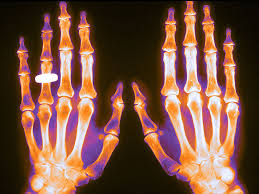

Riesgos infecciosos asociados a los fármacos biológicos utilizados en enfermedades inflamatorias de origen inmune.

El riesgo asociado a las terapias inmunosupresoras se deduce en muchas ocasiones de su mecanismo de acción y establecer una relación causal a veces es complicado. el  objetivo de este boletín fue revisar la evidencia disponible acerca de los riesgos infecciosos relacionados con los fármacos biológicos utilizados en las enfermedades inflamatorias de origen inmune.BIT Navarra, 31 de agosto de 2020